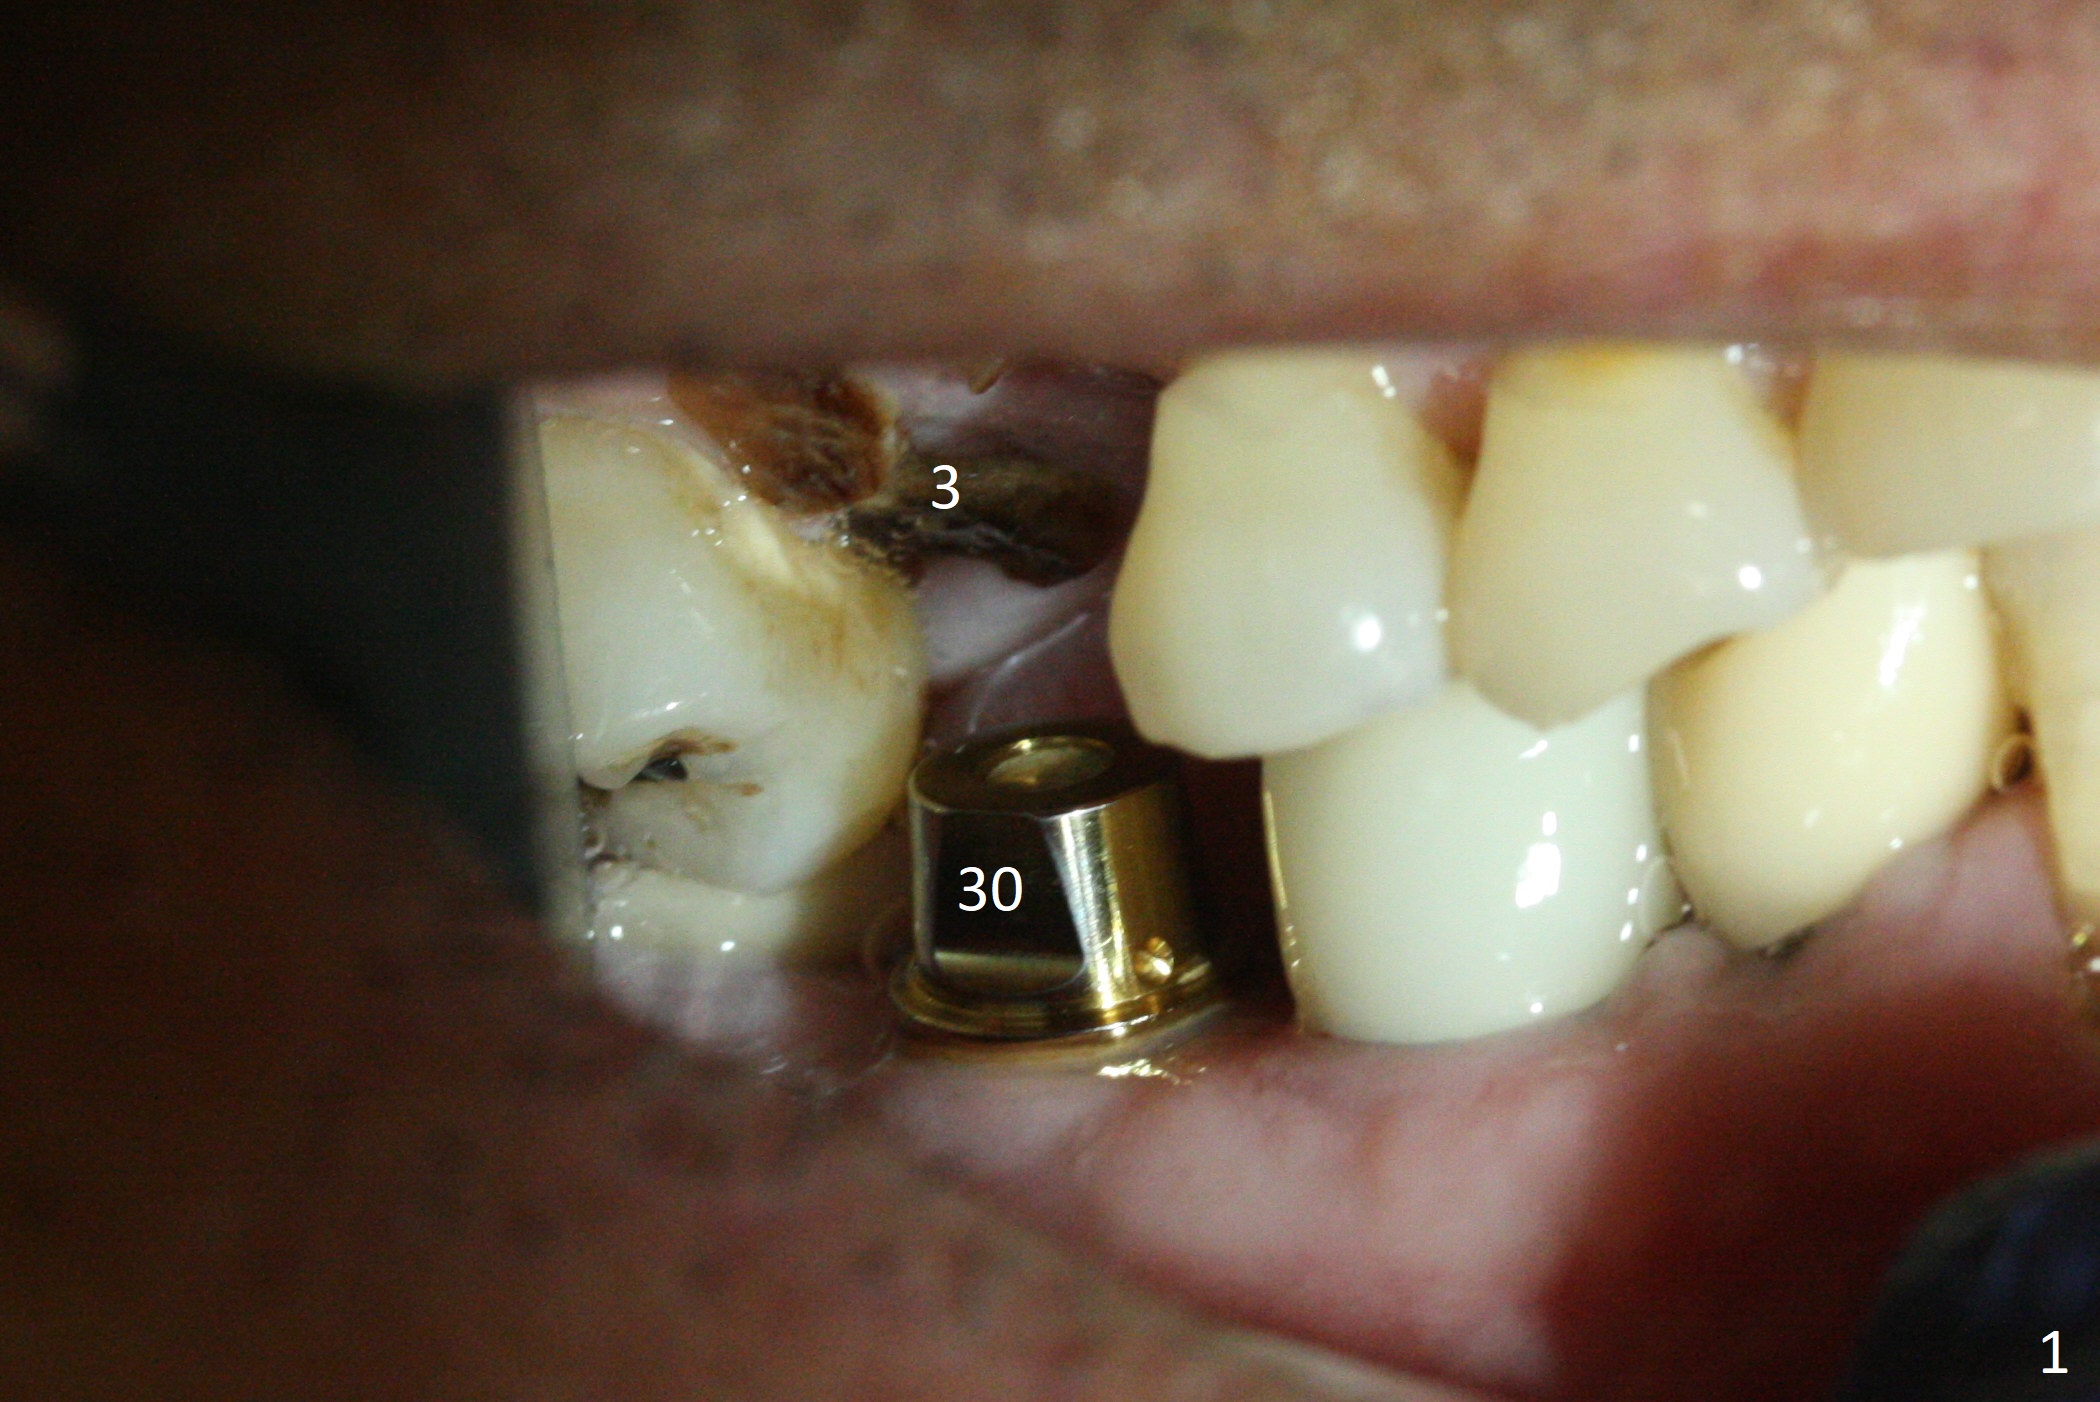

The clearance between the residual roots of the tooth #3 and the abutment at #30 seems to be somewhat limited (Fig.1). The initial osteotomy depth is 10 mm (Fig.2). After moving the osteotomy mesially, the depth increases to 12 mm; a parallel pin is inserted for 16 mm (Fig.3 with sinus membrane perforation). The depth of the rest of the osteotomy is 10 mm with placement of a 5x10 mm implant with >50 Ncm (Fig.4); with insertion of a 6.8x4(3) mm abutment and Vera Graft (*), an immediate provisional is fabricated. Collagen plug is used to seal the gap between the provisional and the gingiva. The abutment dislodges nearly 1 month postop; the wound has healed (Fig.5). A 8.2x5(4) mm healing abutment is placed to keep the soft tissue configurement.